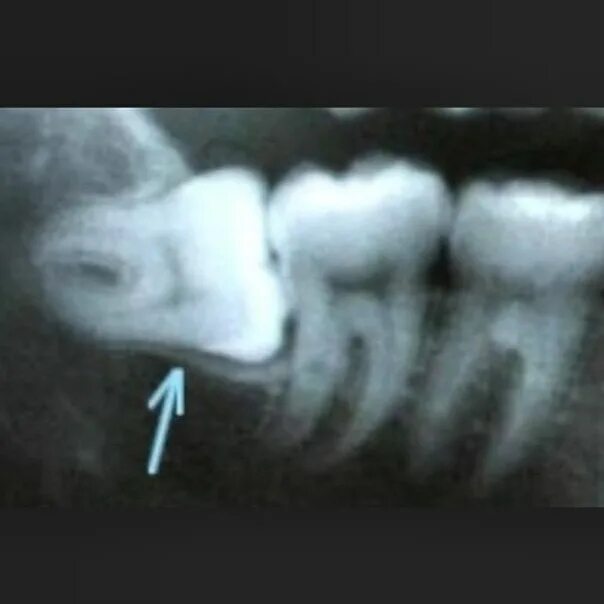

Матрица гаряева зубы и десна